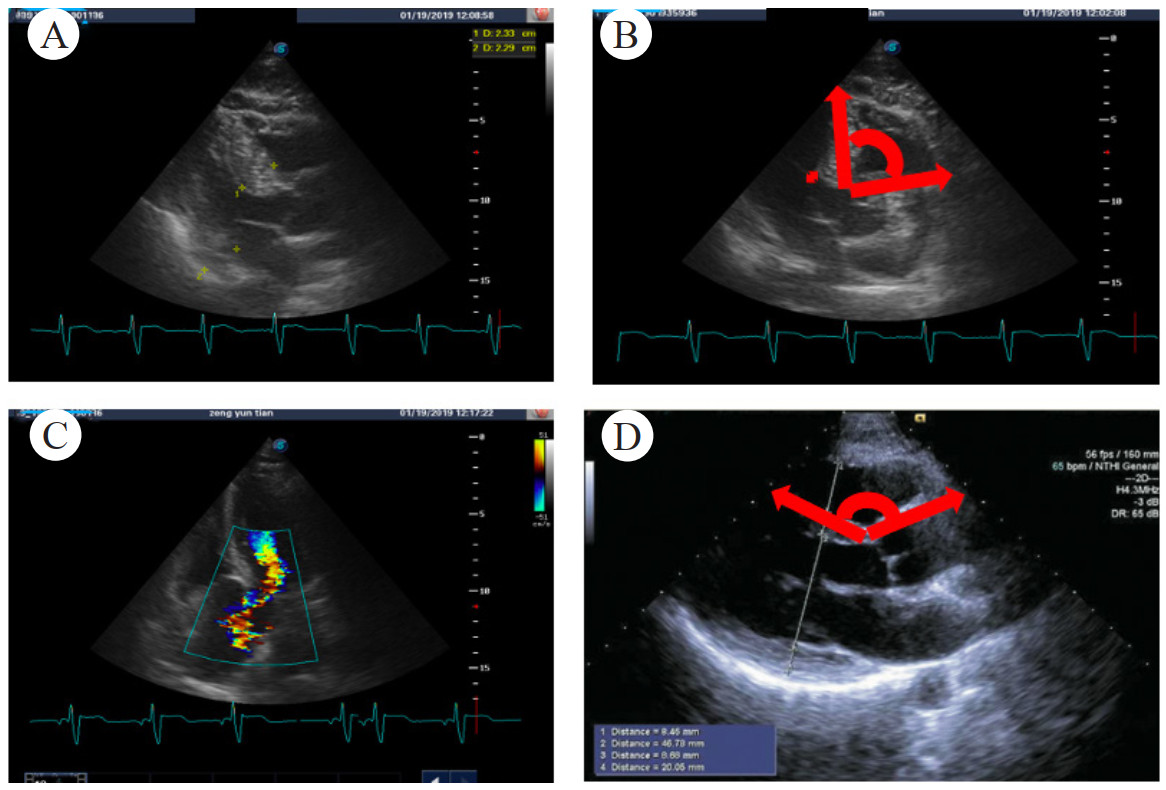

入科后患者肌钙蛋白由0.4 ng/mL升至3.9 ng/mL;氨基末端脑钠肽前体(N terminal pro‐B type natriuretic peptide, NT-ProBNP) > 5 000 pg/mL。2月4日心脏超声提示:左心室肥厚(室间隔13 mm,左心室后壁13 mm),左心室收缩功能正常,左心室射血分数58%,舒张功能降低。心电图提示胸前导联ST-T改变。留置脉波指示连续心排血量监测,心输出量3.2 L/min,每搏量26 mL/次,全心舒张末期容积指数946 mL/m2,全身血管阻力指数4 398 dyn/s/cm5/m2。结合病史,考虑患者脓毒症导致脓毒性心肌病可能性大。2月4日尝试多巴酚丁胺[2 μg/(kg·min)]强心治疗,心率升至130次/min后,动脉血压降至66/44 mmHg;心脏超声提示典型龙虾爪征,左室流出道峰流速达4.4 m/s(图 1)。予以停用多巴酚丁胺后,患者心率降至108次/min,血压恢复至130/69 mmHg。患者抗感染、液体负平衡,复查肌钙蛋白、NT-ProBNP持续下降至正常。2月22日床旁经皮气管切开,并脱离呼吸机。3月1日出院,居家继续康复、护理。随访未再发明显血压波动。

| A、B: 心脏超声左室流出道呈龙虾爪征; C: 二尖瓣前叶收缩期前移 图 1 病例1的超声检查结果 |